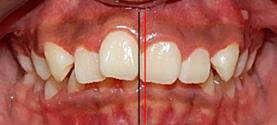

Caso Clínico

Una paciente de 20 años de edad se presenta con el motivo de consulta: “quiero una valoración de ortodoncia”. Estudios clínicos extraorales de inicio se observan quintos proporcionales, línea media superior desviada 1 mm a la derecha con línea media facial (Figura 1), el perfil cóncavo. Tercio inferior aumentado con respecto al tercio medio facial (Figura 2).

Estudios intraorales de inicio

En la fotografía de frente tenemos una mordida abierta anterior, mordida borde a borde posterior bilateral

presencia de hábito de interposición lingual (Figura 3), clase I molar derecha (Figura 4), clase I molar izquierda ( Figura 5 ), línea media facial y dental superior coinciden, línea media facial y dental superior desviada 1 mm a la derecha apiñamiento severo en la arcada superior (Figura 6) y en la arcada inferior.